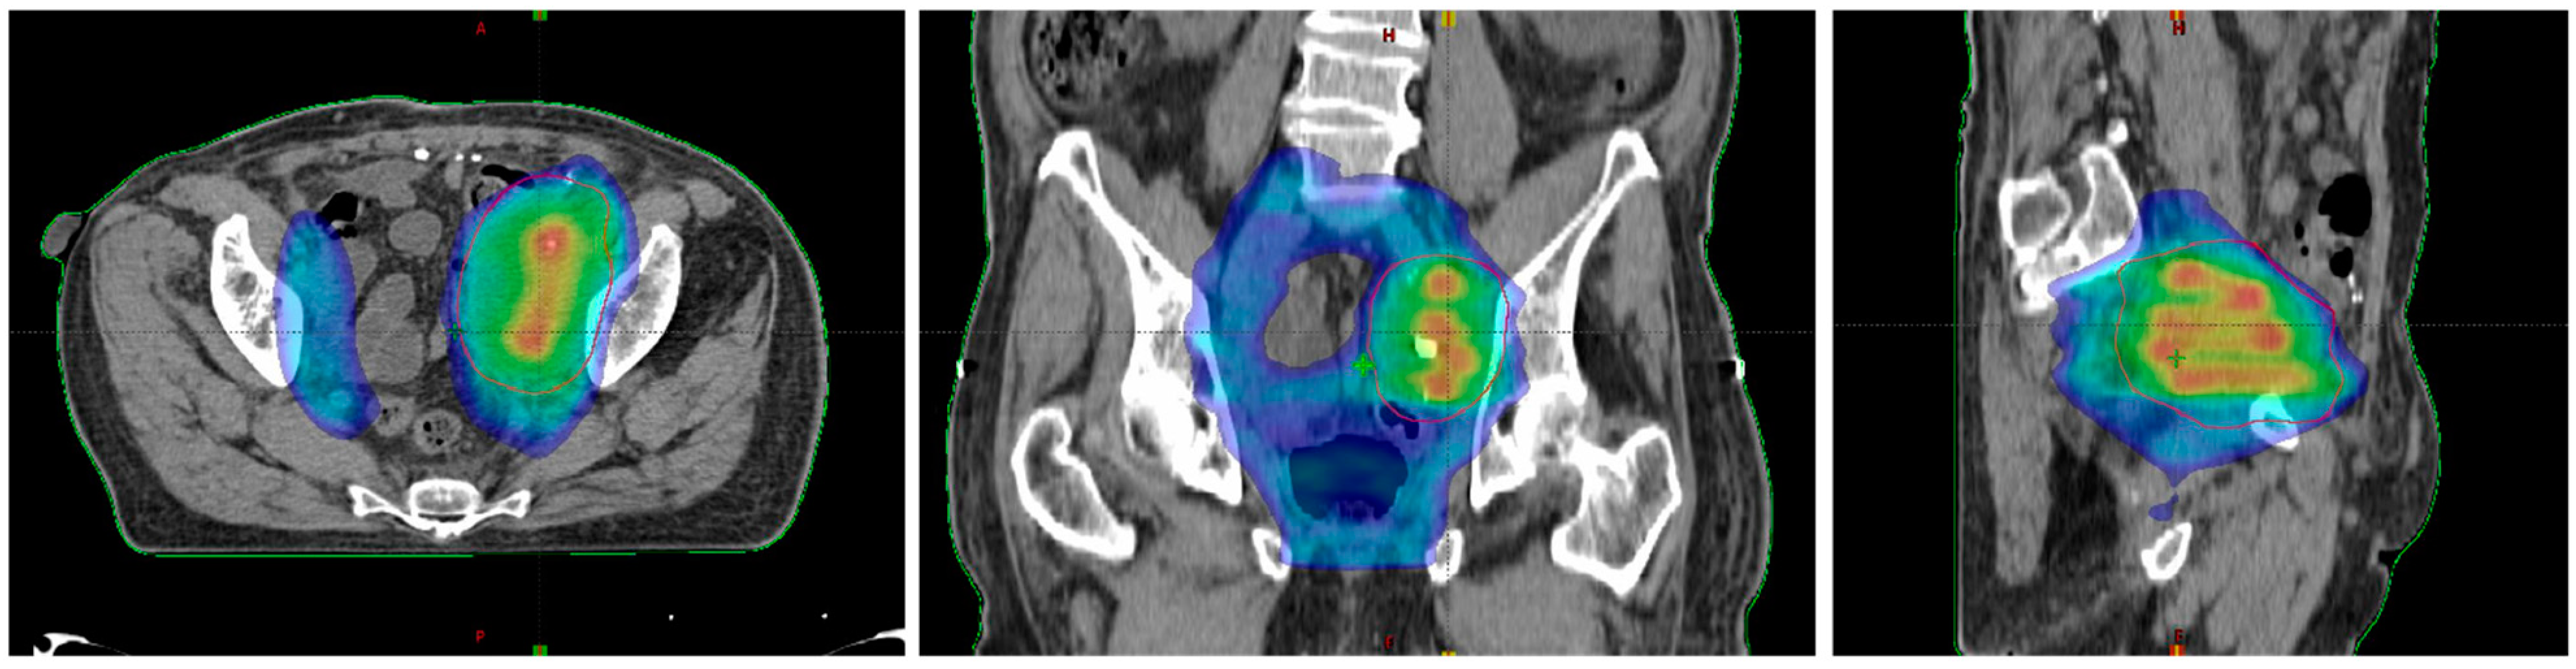

2. Lattice Radiotherapy: Concept

3. Clinical Use of LATTICE Radiotherapy

4. Oxygen-Guided Radiotherapy: Oxygen Is the Needed Comburent for Radiotherapy, Not Only for Fire

5. OGRT in Clinical Practice

- Amendola, B.E.; Perez, N.C.; Mayr, N.A.; Wu, X.; Amendola, M. Spatially Fractionated Radiation Therapy Using Lattice Radiation in Far-advanced Bulky Cervical Cancer: A Clinical and Molecular Imaging and Outcome Study. Radiat. Res. 2020, 194, 724–736. [Google Scholar] [CrossRef]

- Epel, B.; Maggio, M.C.; Barth, E.D.; Miller, R.C.; Pelizzari, C.A.; Krzykawska-Serda, M.; Sundramoorthy, S.V.; Aydogan, B.; Weichselbaum, R.R.; Tormyshev, V.M.; et al. Oxygen-Guided Radiation Therapy. Int. J. Radiat. Oncol. 2019, 103, 977–984. [Google Scholar] [CrossRef]

- Epel, B.; Redler, G.; Pelizzari, C.; Tormyshev, V.M.; Halpern, H.J. Approaching Oxygen-Guided Intensity-Modulated Radiation Therapy. Single Mol. Single Cell Seq. 2016, 876, 185–193. [Google Scholar] [CrossRef] [Green Version]

- Epel, B.; Maggio, M.; Pelizzari, C.; Halpern, H.J. Electron Paramagnetic Resonance pO2 Image Tumor Oxygen-Guided Radiation Therapy Optimization. Chem. Biol. Pteridines Folates 2017, 977, 287–296. [Google Scholar] [CrossRef]